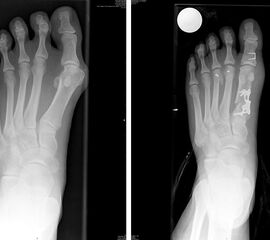

• Winkelstabiles Implantat (z.B. TOM Platte der Firma Wright Medical).

Die TOM Platte wurde für eine gerade bikortikale Osteotomie am MT 1 entwickelt (Thomas M. 2009). Durch die v-förmige Osteotomie ergibt es sich relativ häufig dass die Platte besser am Knochen anliegt wenn sie seitenverkehrt angebracht wird d.h. die Platte mit der Aufschrift R am linken Fuß und umgekehrt. Das nicht winkelstabile Gleitloch sollte sich immer distal der Osteotomie befinden.

• Röntgenkontrolle am ersten postoperativen Tag, nach 3 und 6 Wochen.

Ergebnisse

Die OP Methode hat sich als Standardeingriff bei größeren Hallux valgus Fehlstellungen etabliert. Der Intermetatarsale Winkel kann sehr gut korrigiert werden. Der Erste Strahl wird stabilisiert und kann wieder Last aufnehmen. Die Verwendung einer winkelstabilen Plattenosteosynthese zur Fixation einer proximalen Osteotomie am MT 1 hat sich bereits bewährt123, insbesondere auch mit der hier verwendeten TOM Platte (Thomas M. 2009). Die V-förmige Knochenschnittführung bietet eine zusätzliche Stabilität.

Häufig wird additiv eine Akin Osteotomie durchgeführt. Irritationen über der tastbaren Platte führen in vielen Fällen zur Metallentfernung. Eine Studie zur Auswertung der Ergebnisse wurde begonnen.